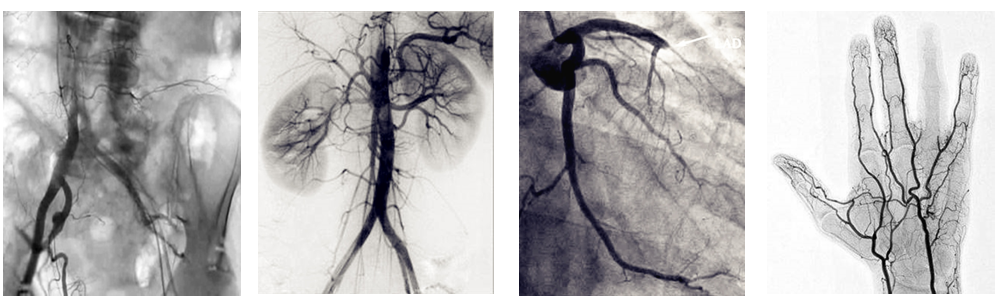

介入c臂機(jī)可以把不需要的組織影像刪除掉,只保留血管影像。圖像清晰,分辨率高,對(duì)觀察血管病變,血管狹窄的定位測(cè)量,診斷及介入治療提供了真實(shí)的立體圖像,還具有多種工作模式,靈活方便,滿足各種臨床需要,為各種介入治療提供了必備條件。

普愛(ài)醫(yī)療PLX7100A數(shù)字移動(dòng)式C型臂X射線機(jī)是為周邊介入治療而設(shè)計(jì)的移動(dòng)式平板介入c臂機(jī),配備新型的非晶硅動(dòng)態(tài)平板探測(cè)器,使之成為一款更加貼合介入臨床需求的移動(dòng)式介入設(shè)備。下面小編給大家介紹下我公司介入c臂機(jī)臨床應(yīng)用及性能特點(diǎn):

PLX7100A移動(dòng)式介入c臂機(jī),體積小,劑量低,圖像清晰,是廣大基層醫(yī)院介入腫瘤科以及三甲醫(yī)院專科介入(如肝膽外科、ERCP室、婦科)使用的理想設(shè)備。